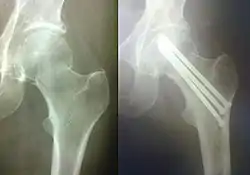

Рентгенограми кінцівок після остеосинтезу

Остеосинтез плечової кістки інтрамедулярним стержнем одразу після операції та після зрощення, малоінвазивне виконання (мінімальні розрізи), за час загоювання пацієнт користується кінцівкою